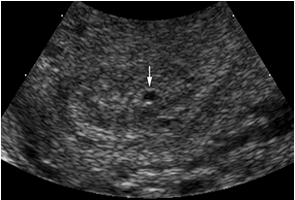

Type B: lớp dịch lòng tử cung có hình ảnh là nang echo trống, bờ đều đặn. Hình ảnh này gặp ít hơn hình ảnh type A (tỷ lệ < 25%).

Kết luận của nghiên cứu: tỷ lệ có ứ dịch lòng tử cung ở những trường hợp thai ngoài tử cung 16,6%. Siêu âm ngả âm đạo giúp phát hiện có thai, chẩn đoán phân biệt thai ngoài tử cung và thai trong tử cung có thể dựa vào hình dạng, vị trí, cấu trúc bên trong và đường viền của lớp dịch trong lòng tử cung.